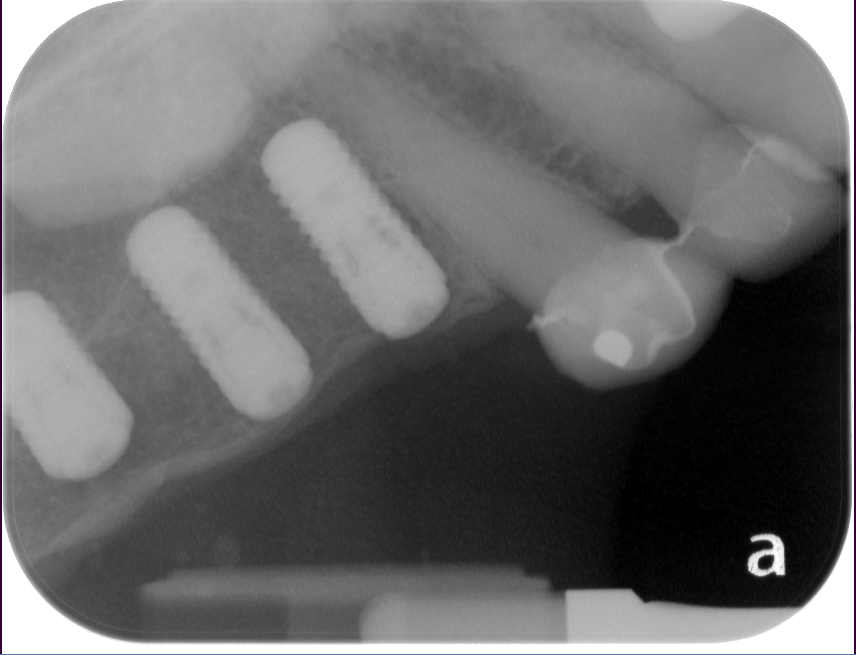

Sinus Lift, Bone Graft, Implants Dr. Noroozi IMPrESS Perio Implant Center

The bone used in a sinus lift may come from your own body (autogenous bone), from a cadaver (allogeneic bone) or from cow bone (xenograft). You will need X-rays taken before your sinus lift so the dentist can study the anatomy of your jaw and sinus. You also may need a special type of computed tomography (CBCT) scan. This scan will allow the dentist to accurately measure the height and width of your existing bone and to evaluate the health of your sinus.